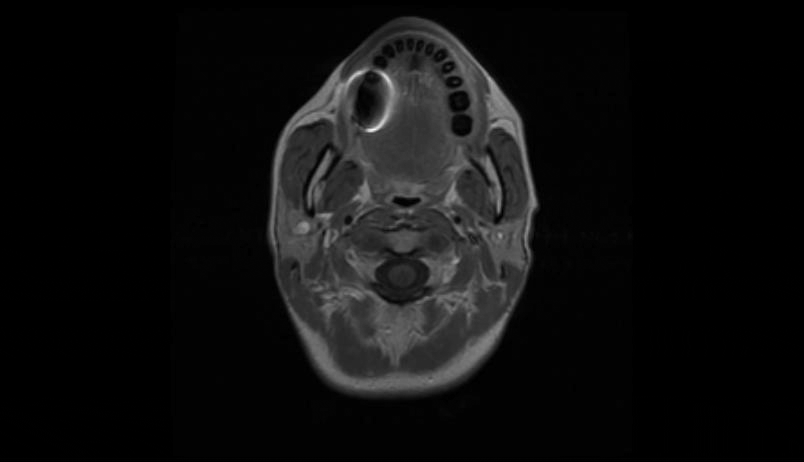

MRI of the cervical and thoracic spine showed a diffuse, intramedullary abnormal signal extending from the medulla down to approximately the mid-thoracic level. There was swelling in portions of the spinal cord, particularly in the lower cervical cord where there was contrast enhancement (Figure 1 [Fig. 1], Figure 2 [Fig. 2], Attachment 1 [Att. 1]). The MRI of the brain was normal.

Figure 2: MRI of the cervical spine, coronal view: contrast enhancement in the lower cervical cord